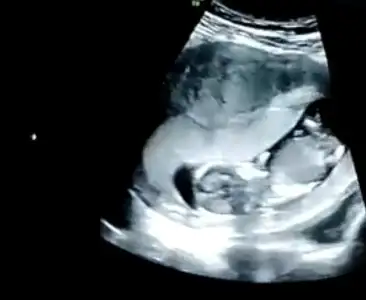

Ikra meyra Ikra meyra 13+1 haftalık karından ultrason görüntülerini yorumlayabilir misin?☺️🙏

• E3F032FD-DEC1-441B-9C2F-74E6BCB4031B.webp

E3F032FD-DEC1-441B-9C2F-74E6BCB4031B.webp

13,5 KB · Görüntüleme: 99

• 1E453C56-2138-42C3-9A0B-B911010748C2.webp

1E453C56-2138-42C3-9A0B-B911010748C2.webp

12,2 KB · Görüntüleme: 84

• F81223CF-67E7-4B27-B053-CC32C3F726AA.webp

F81223CF-67E7-4B27-B053-CC32C3F726AA.webp

12,9 KB · Görüntüleme: 86

• D728CB6D-3F87-43E7-8DE5-94A417DDF0F3.webp

D728CB6D-3F87-43E7-8DE5-94A417DDF0F3.webp

17 KB · Görüntüleme: 109